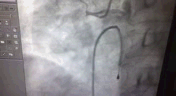

20 分钟后安全地将患者送到介入室,先为患者安装临时起搏器,心率维持在 80 次/分,血压基本恢复正常。冠脉造影结果提示,犯罪血管正是右冠状动脉,起始端严重闭塞。

予以血栓抽吸导管,抽出一条长约 2cm 的血栓。

导丝逐渐疏通右冠。

球囊导入导丝,撑开右侧冠状动脉。

我们可以看到右冠已经基本疏通,心内科医生考虑到患者基础身体差,只能为患者择期安装支架。向家属告知手术十分成功,但是患者下壁联合右室心梗,长达 40 多个小时,心肌基本坏死,而且逐渐出现休克症状,患者可以说是九死一生。